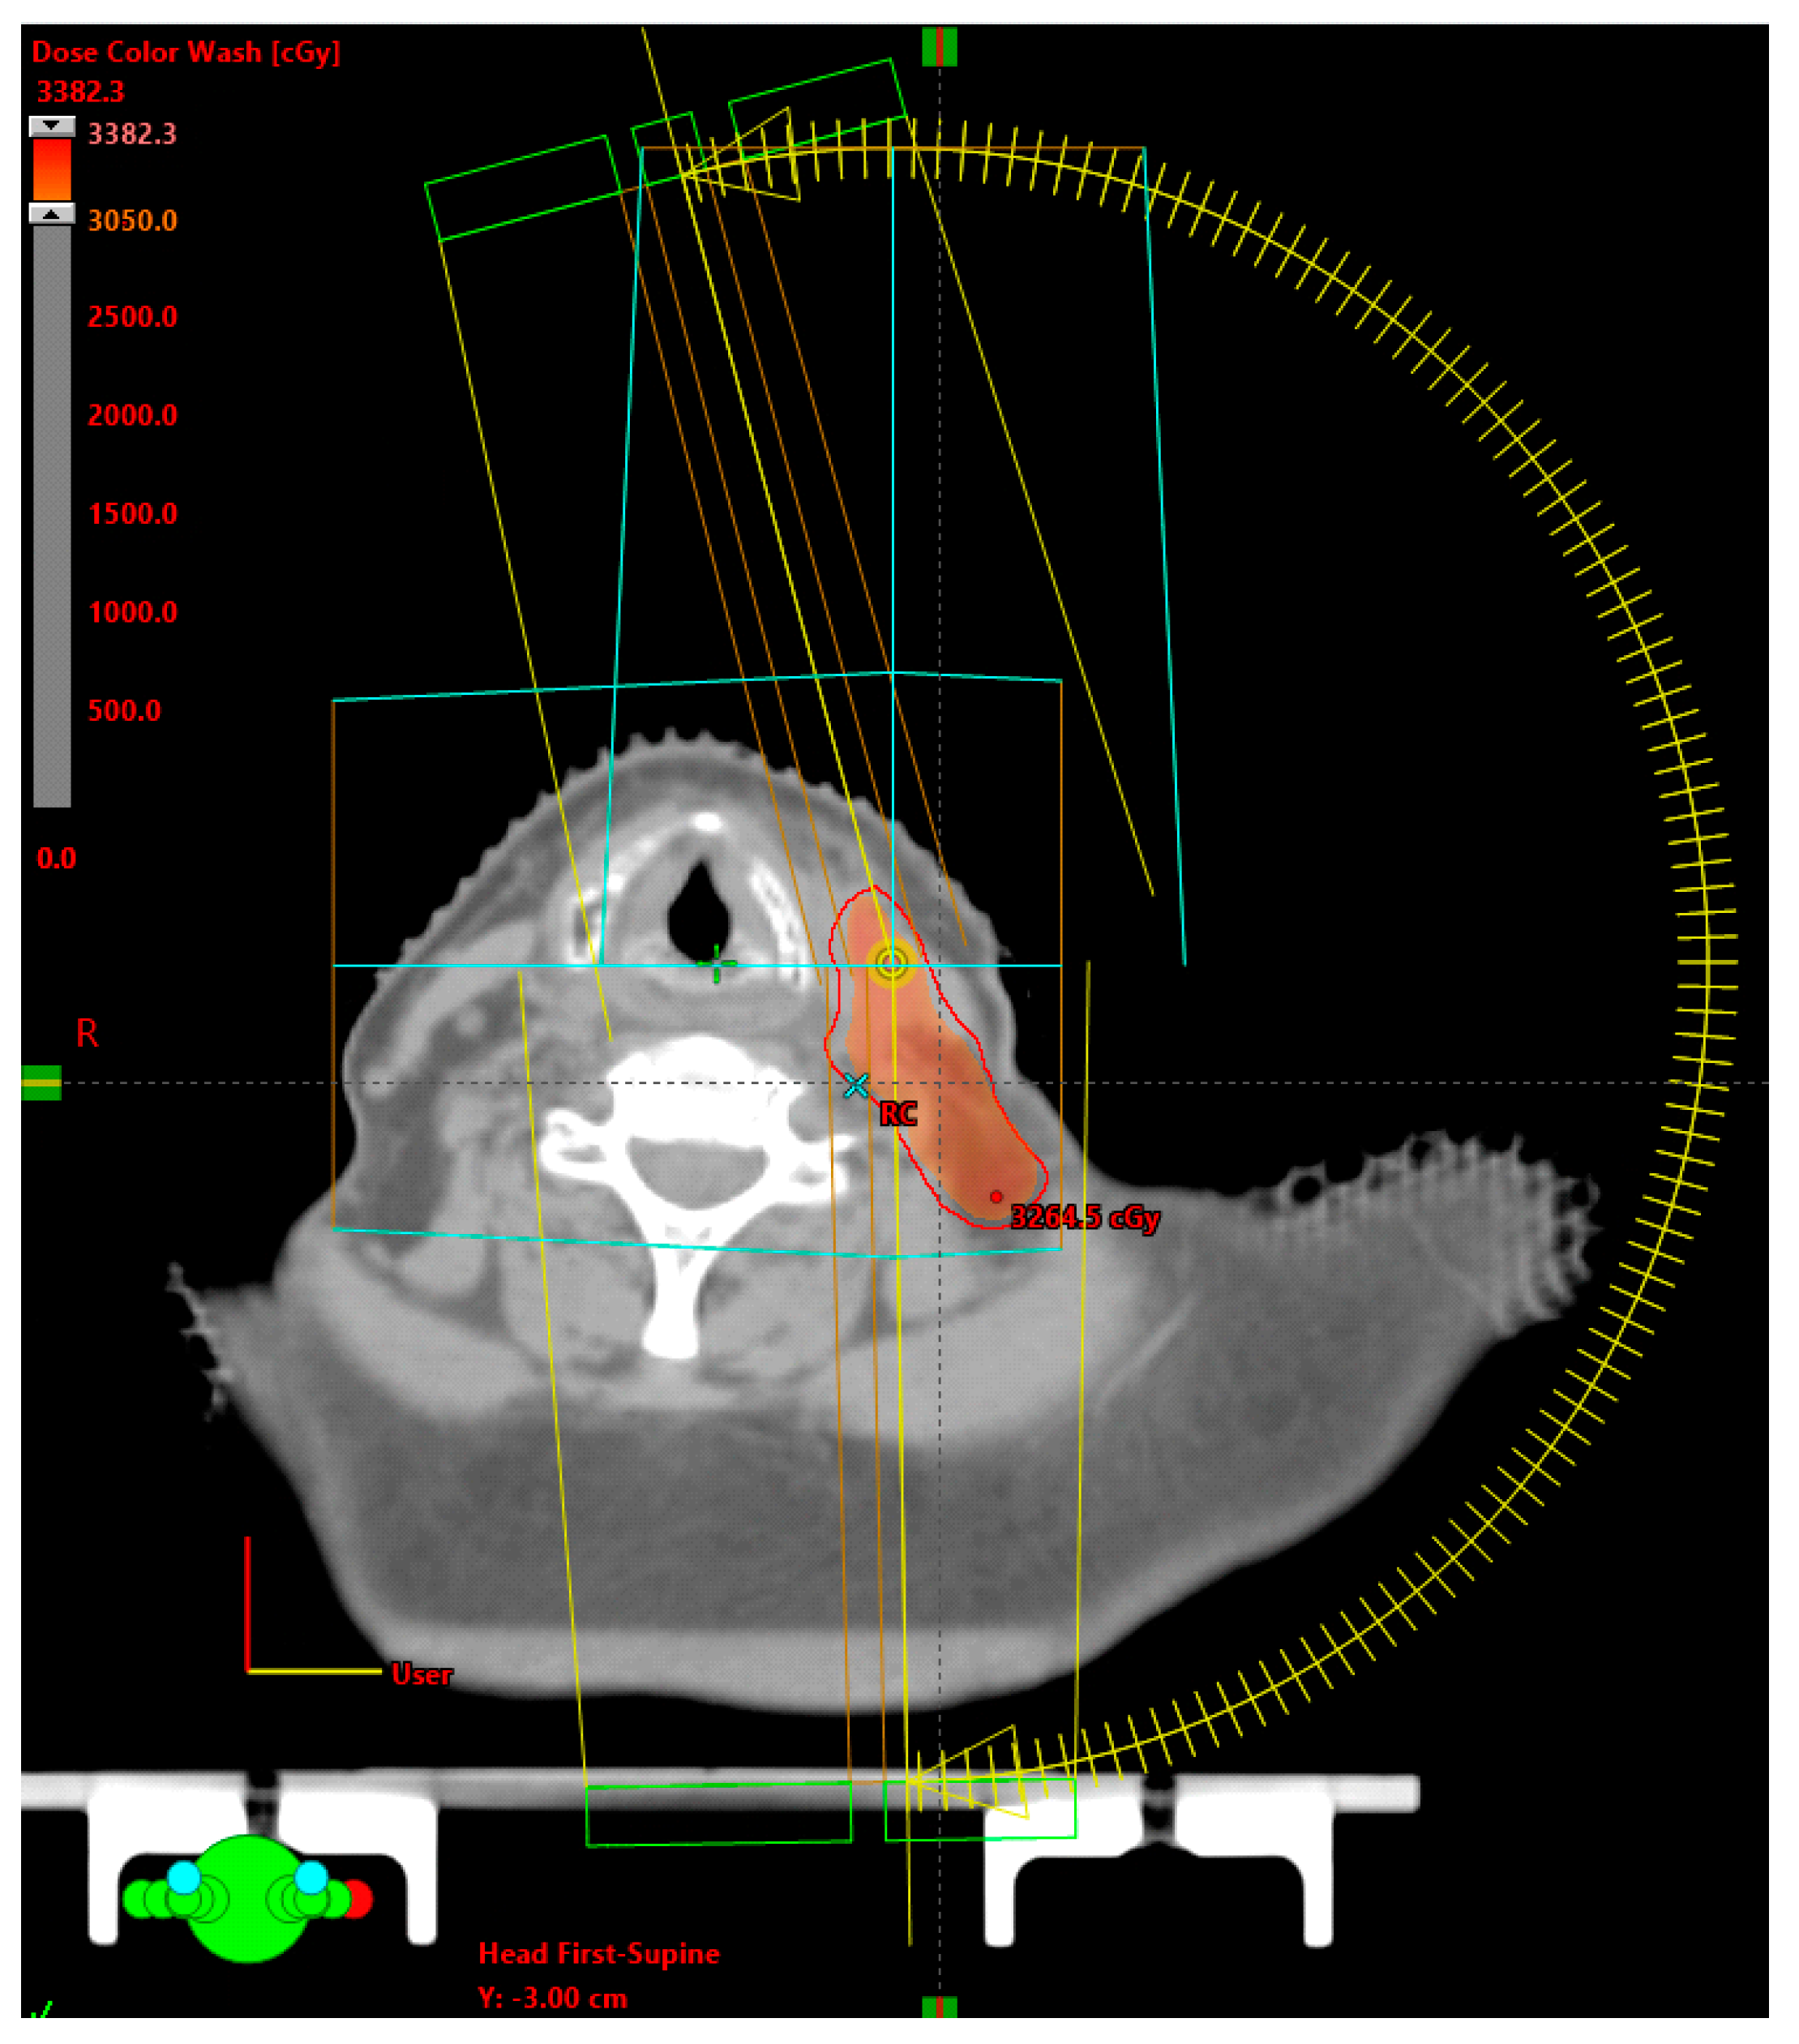

2. Patients and Methods

3. Radiation Plan and Dose Delivery